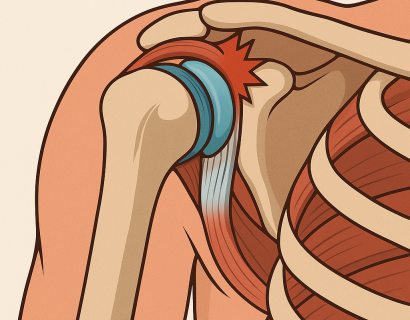

Импиджмент (от англ. impingement — "сдавливание, защемление") — это не самостоятельное заболевание, а синдром, при котором мягкие ткани плеча (сухожилия, бурса) ущемляются между костными структурами во время движений руки.